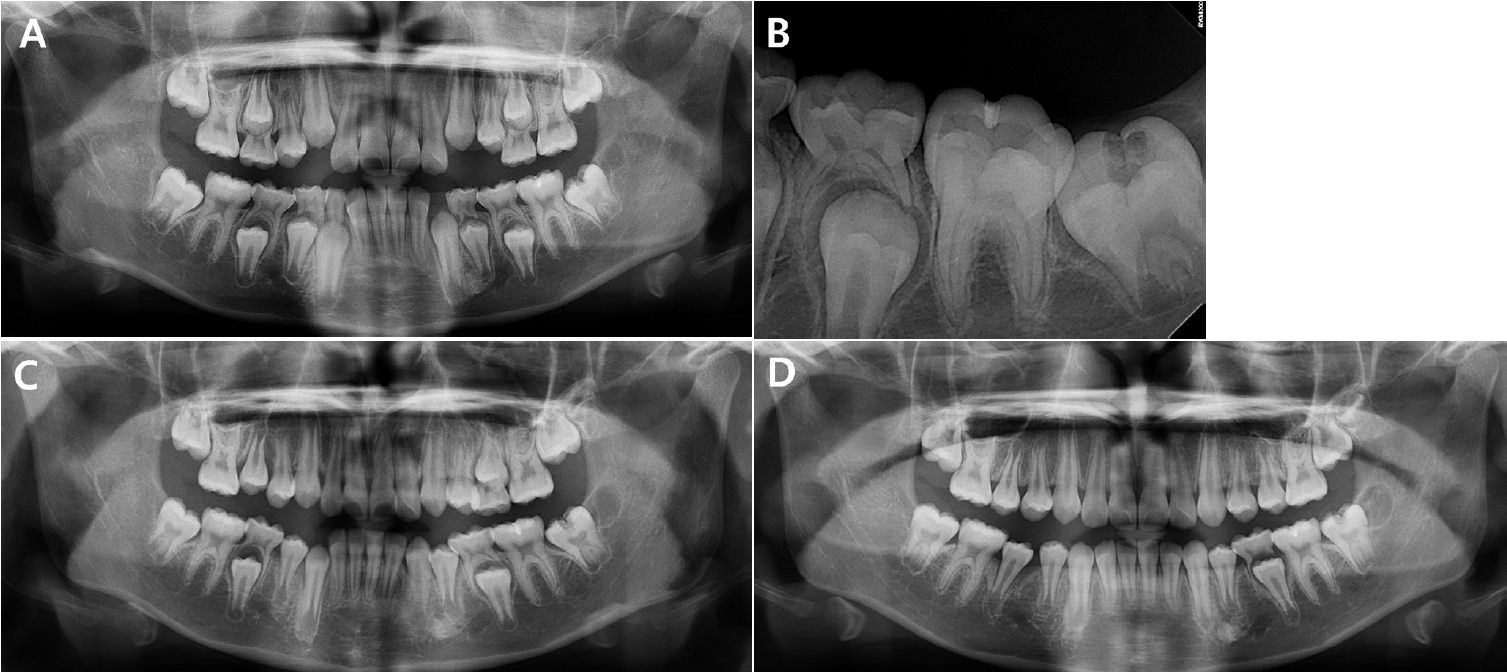

Figure 1.

Preoperative radiographs. A radiolucent lesion is observed in the coronal portion of tooth #37. A. Panoramic view at the initial visit. B. Periapical view at the initial visit. C. Panoramic radiographs taken during the follow-up period. At 6 months, an eruptive pattern of tooth #37 is observed. D. At 12 months, tooth #47 begins to emerge through the gingiva.

10세 여아가 미맹출된 하악 좌측 제2대구치의 방사선 투과상이 관찰된다는 주소로 개인 의원에서 조선대학교 치과병원 소아치과에 의뢰되었다. 환아는 특이 의학적 병력이 없었고, 임상적으로도 증상은 나타나지 않았다. 내원 당시 구강 내 임상 검사에서는 특이 소견이 관찰되지 않았으며, 방사선학적 검사에서 미맹출된 하악 좌측 제2대구치의 치관부에 방사선 투과상이 확인되어 PEIR으로 진단하였다(Figs. 1A and B).초진 당시 병소의 위치가 깊어 치은판절제술을 시행하더라도 접근이 어려울 것으로 판단되었으며, 이에 따라 6개월 간격의 정기검진을 통해 병소의 진행 양상과 맹출 상태를 관찰하며 적절한 치료 시기를 결정하기로 하였다.6개월 후 내원하여 촬영한 파노라마방사선사진에서 해당 치아의 맹출이 진행 중인 것이 확인되었고, 병소의 크기나 형태에는 변화가 없어 추가 맹출 이후 수복하기로 계획하고 6개월 뒤 재내원을 안내하였다(Fig. 1C). 초진으로부터 12개월 경과 시 하악 좌측 제2대구치는 여전히 출은하지 않았으나, 하악 우측 제2대구치의 출은이 확인되어 내원 간격을 3개월로 조정하였다(Fig. 1D).3개월 후 재내원 시 하악 좌측 제2대구치의 출은이 관찰되어 수복 치료를 시행하기로 결정하였다(Fig. 2A). 국소마취하에 치은판 절제술을 시행하여 치관 전반을 노출하였고 협면과 교합면에 걸쳐 흡수성 와동이 확인되었다. 특히 협측에 깊은 병소가 존재하였으며, 와동 내부는 연조직으로 채워져 있었다. 병소를 저속 핸드피스와 수기구를 이용하여 제거한 후, 광중합형 GI (Riva Light Cure, SDI, Victoria, Australia)로 충전하였다.- 증례 2